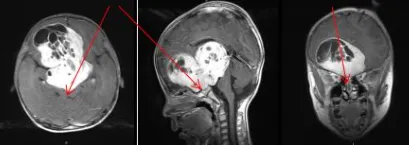

术前:首次术后状况无明显改善

5岁的男孩患有巨大视路胶质瘤,第一次术后鞍区及三脑室肿瘤残余较大,双侧视神经被肿瘤侵犯,下丘脑也被严重挤压,左侧脑室积水明显,状况并没有得到明显改善。

第一次术前